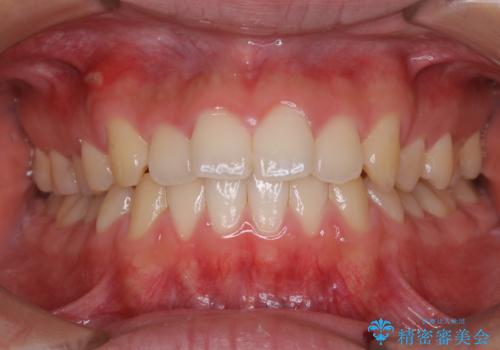

[ 前歯のねじれ・がたつき ] マウスピース矯正

![[ 前歯のねじれ・がたつき ] マウスピース矯正の症例 治療前](https://seimitsushinbi.jp/wp/wp-content/uploads/2024/02/4007c6479f6bce11863dcdd32ed5e39b-500x350.jpg?v=1708502552)

![[ 前歯のねじれ・がたつき ] マウスピース矯正の症例 治療後](https://seimitsushinbi.jp/wp/wp-content/uploads/2024/02/e7a01485e4f4dd0da04705fde4cc34cc-500x350.jpg?v=1708502585)